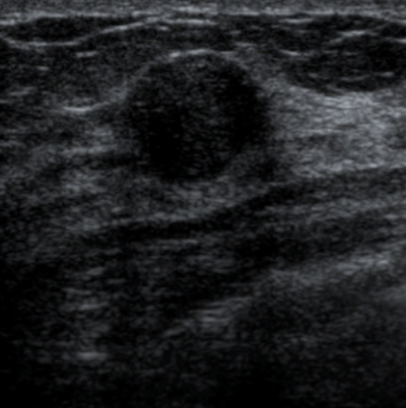

Solid mass

(as on USS; solid tissue appears as varying shaded of grey)